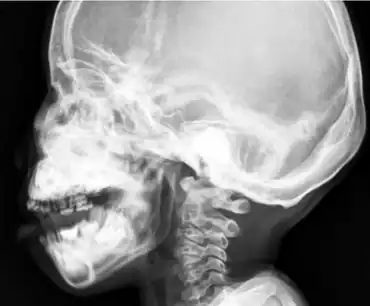

| Sclerosis and hyperostosis of the skull base, maxilla, and mandible. | |

Craniometaphyseal dysplasia is diagnosed based on clinical and radiographic findings that include hyperostosis. Some things such as cranial base sclerosis and nasal sinuses obstruction can be seen during the beginning of the child's life. In radiographic findings the most common thing that will be found is the narrowing of foramen magnum and the widening of long bones. Once spotted treatment is soon suggested to prevent further compression of the foramen magnum and disabling conditions.